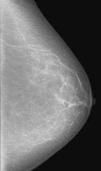

Descriptores BI-RADS de distribución de las microcalcificacionesEste descriptor se refiere a la disposición de las calcificaciones en el interior de la mama y, con relación a la probabilidad de malignidad, es tan importante como la morfología12,13. En la figura 1 se observa un esquema que ilustra los diferentes descriptores de distribución utilizados en las categorías BI-RADS.

Esquema de los descriptores BI-RADS de distribución de las microcalcificaciones.